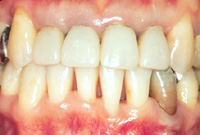

顎の位置、歯の位置が正しくなることにより、歯肉の形も調和がとれてきました!